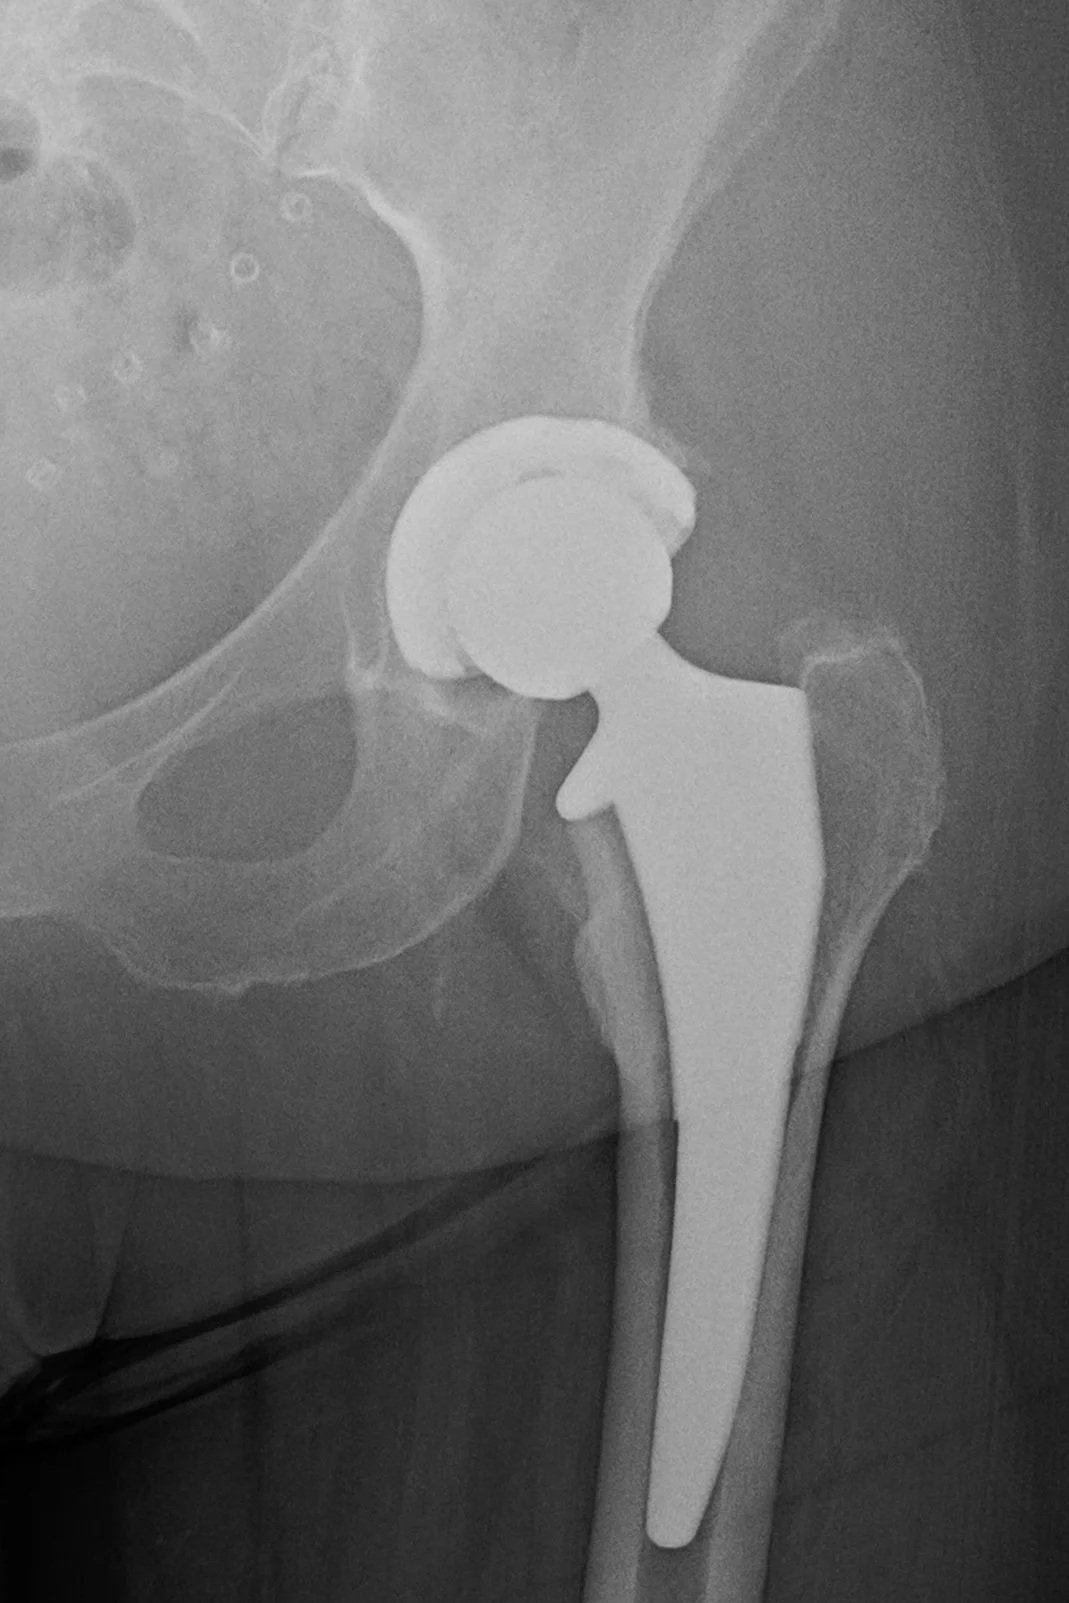

Anterior Total Hip Replacement

Anterior total hip replacement performed using muscle-sparing techniques to support early mobility and structured recovery.

Yes. Anterior total hip arthroplasty is offered when appropriate. This muscle-sparing approach may allow for early mobility and functional recovery, depending on patient anatomy and clinical considerations.